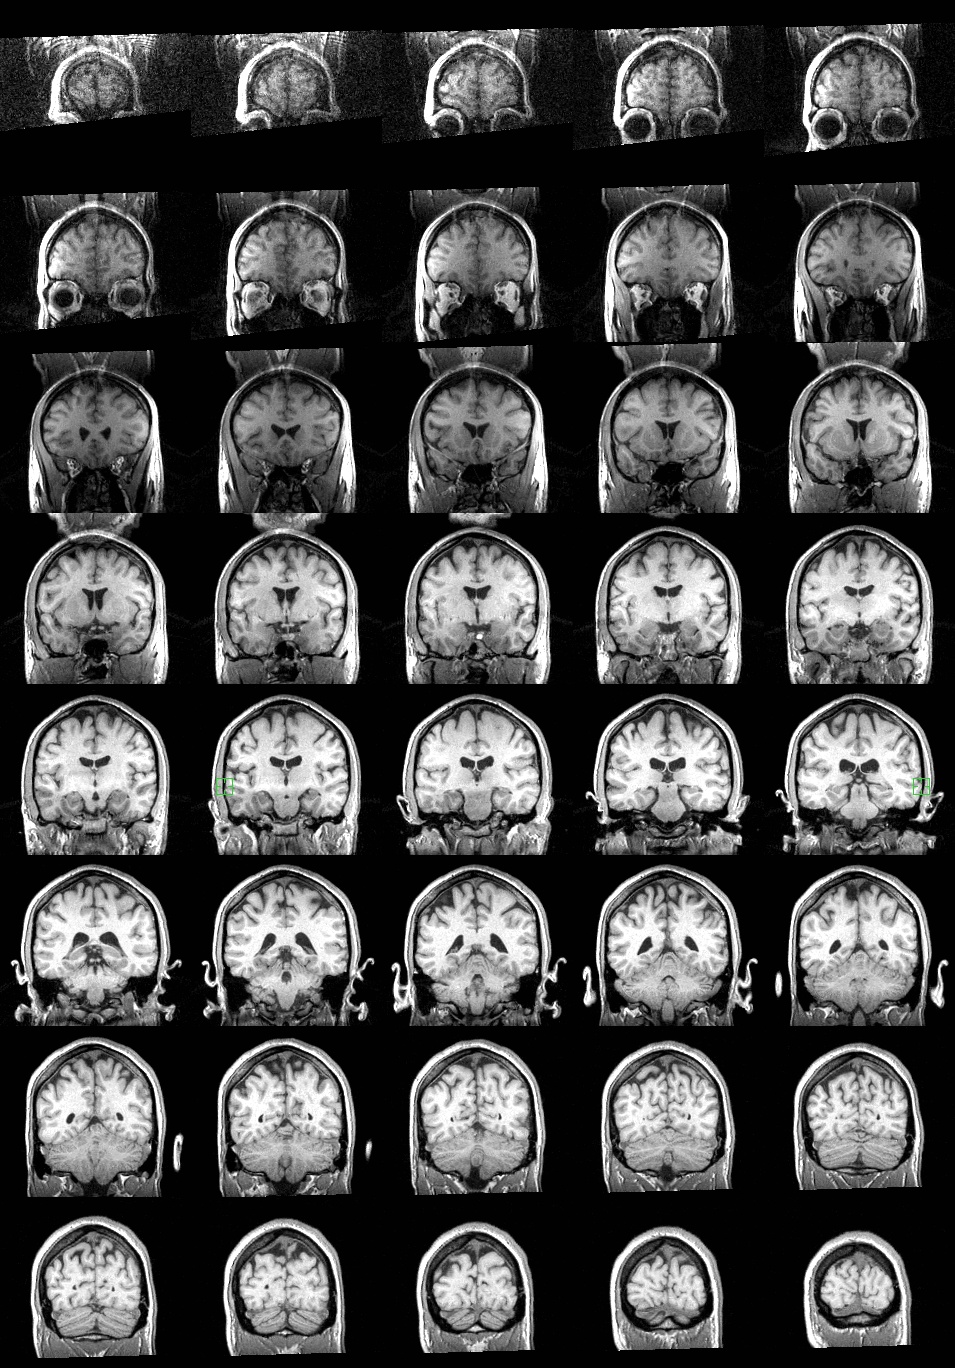

Coronal slices: These images go from anterior in the upper left to posterior in the lower right. Again, image left side represents brain left side; thus, the view you get is opposite what you would see if you were facing the brain (ahem) head-on. |